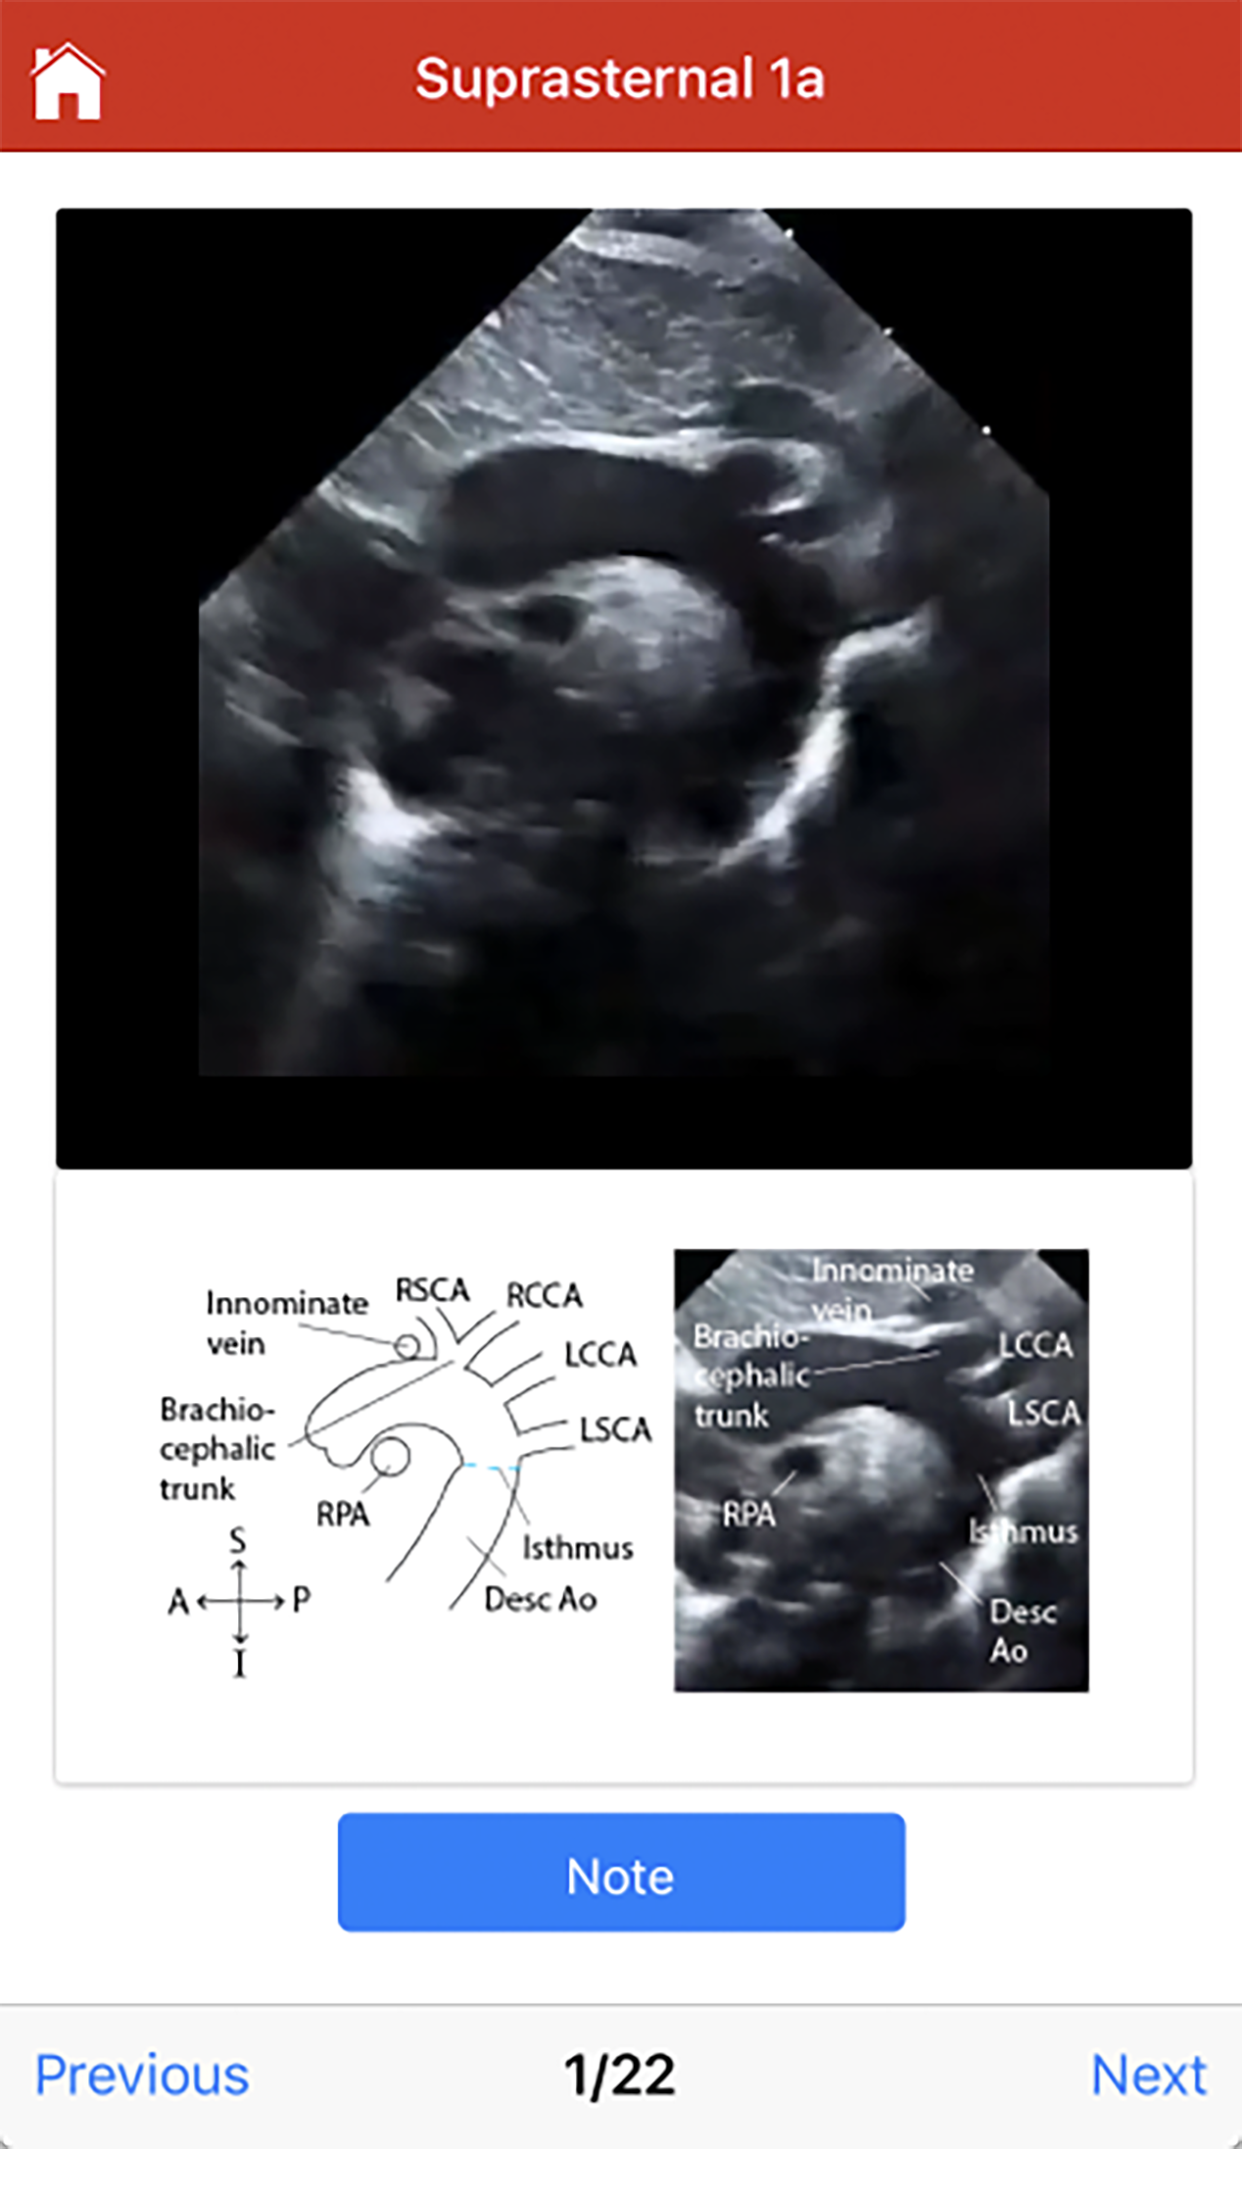

The Echo app provides step-by-step instructions for performing a normal pediatric echocardiogram and uses video clips, images and illustrations to aid in instruction. The app is intended to be used by sonographers at all levels of training, pediatric cardiology fellows, as a teaching aid for pediatric cardiologists and by anyone interested in learning how to perform the normal pediatric echo exam. There are four standard views where images can be obtained: 1. Subcostal 2. Parasternal 3. Apical 4. Suprasternal The exact images and the order in which the images and views are obtained varies by institution. Each protocol (subcostal, parasternal, apical or suprasternal) can be followed in order by clicking on the next tab at the bottom of the page or you can click on an individual numbered view within the protocol list to be taken directly to that view. The name of the view and instructions will pop-up automatically at the bottom of the page. The instructions and additional notes can also be found in the “NOTE” button at the bottom of the page. About The Pediatric and Adult Congenital Heart Program at American Family Children’s Hospital The UW Health Pediatric and Adult Congenital Heart Program consists of a highly experienced team providing diagnostic, interventional and surgical services. We are committed to providing the best outcomes for children and adults with congenital heart disease as well as for children with acquired heart issues. Our goal is deliver remarkable care that exceeds expectations in partnership with our patients, families and referring physicians. You can learn more about the UW Pediatric and Adult Congenital Heart Program at uwhealthkids.org/hearts. Development The content and illustrations were created by Margaret Greco, MD. For questions regarding the app, contact: mmgreco@pediatrics.wisc.edu The mobile application was developed by Jonah Pelfrey. To reach out to the developer, please contact: pelfreyjonah@gmail.com A special thank you to J. Carter Ralphe MD, Ellen Wald MD, Catherine Allen MD, Derek Hoyme MD, Shardha Srinivasan MBBS, John Hokanson MD, Nicholas Von Bergen MD, John Hambrook MD, Matthew Smith PhD, JoAnne Weber BS, RDCS, RVT, James Bednarz RDCS, FACE, Jamie Beebe RDCS, Jennifer Lassiter RDCS, RVT, Michael Miller RDCS, and the entire Heart Program Team. The Echo app is made available to the sonography community as a service in connection with the University of Wisconsin-Madison’s outreach mission. It is intended as a training resource for sonographers, but is not a substitute for other forms of training. THE UNIVERSITY EXPRESSLY DISCLAIMS ANY AND ALL WARRANTIES IN CONNECTION WITH THE ECHO APP, INCLUDING BUT NOT LIMITED TO WARRANTIES OF FITNESS FOR A PARTICULAR PURPOSE, WARRANTIES OF MERCHANTABILITY, AND WARRANTIES OF NON-INFRINGEMENT. By using the Echo app, you acknowledge and agree to the foregoing and waive any and all claims of any kind and description against the Board of Regents of the University of Wisconsin System, its officers, employees and agents, in connection with your use of the Echo app and any decisions you may make as a result of using the Echo app.